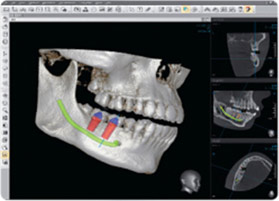

La radiología dental 3D ofrece al odontólogo informaciones muy detalladas para un diagnóstico más preciso y una mayor precisión en el tratamiento. La radiografía 3D le ofrece una visión más completa de la anatomía facial - prácticamente desde cualquier ángulo y perspectiva. Algo imposible de ver con imágenes 2D.

La radiología dental 3D es rápida y sencilla: en tan sólo segundos de escaneado le ofrece un estado completo de la zona bucal, maxilar y dental del paciente. Estas informaciones precisas y extensas pueden ayudarle a asesorar aun mejor a sus pacientes.

Visualiza la zona bucal, maxilar y dental desde una gran variedad de perspectivas

Puede ampliar cada área e incluso girarla

Nada permanece oculto: con la radiología dental obtendrá una imagen completa de la estructura oral, incluidos los huesos maxilares, estructuras blandas y nervios - todo ello con un único escaneado

Planificación y realización mejorada de implantes